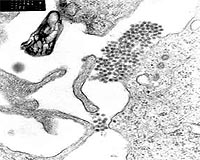

Reporting in Thursday's issue of Nature, researchers led by Shie-Liang Hsieh of the National Yang-Ming University in Taipei say that the cytokine storm is unleashed by interaction between the dengue virus and a molecule called CLEC5A located on immune cells.

They used antibodies on lab mice to interfere with the contact between the virus and the CLEC51. They found that this prevented inflammation but did not prevent the rest of the immune system from operating normally against infection. Fifty percent of mice treated with the antibodies were able to get rid of the virus.